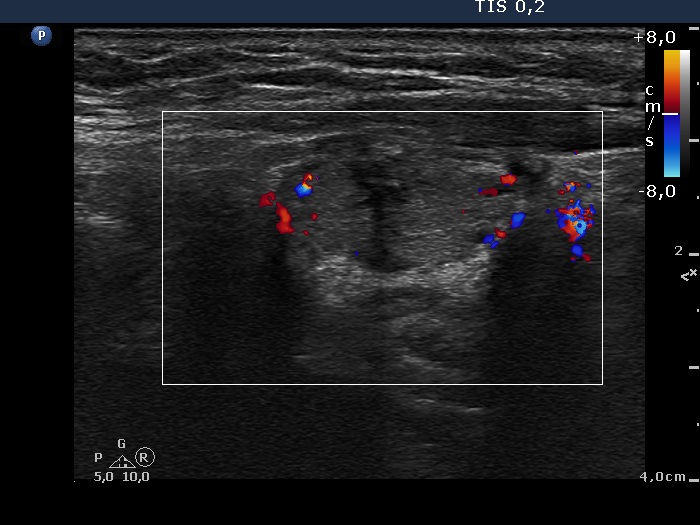

Six months after surgery (ultrasonographic picture 7)

Right lobe, longitudinal scan

Left lobe, longitudinal scan, color Doppler mode.